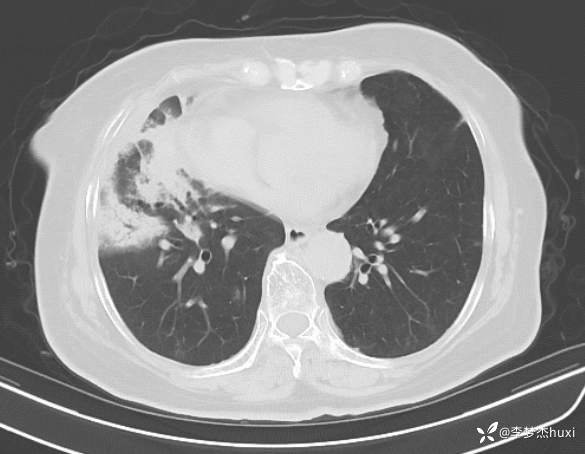

女性77岁,肺癌2年余,此次发热、肺炎,可能是什么病原菌感染?

.既往室上速病史10余年,期间7-8年未反复,近期症状平稳,未口服药物治疗,2008年因胰腺囊肿,当时未明确性质,行脾脏、胆囊、胰腺部分切除术;2021-8发现右肺占位,予穿刺活检,病理示腺癌,诊断右肺腺癌(T4N2M1a IV期)肺内多发转移 纵隔淋巴结转移,给予化疗联合免疫治疗,期间肿瘤增大,给予放射性粒子植入,后肿瘤逐渐缩小,帕博利珠单抗应用2年后停用,肿瘤处于稳定状态;确诊糖尿病病史2年余,目前口服降糖药物治疗,

临床诊断:肺炎